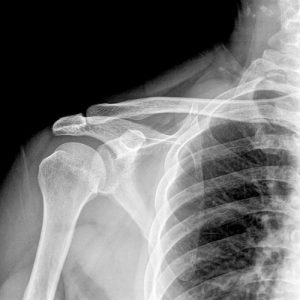

Orthopaedic trauma is any severe injury to the bones, joints, and/or soft tissue that is caused by an external source. It encompasses a wide spectrum of injuries, from simple hairline fractures to life-threatening accidents. Many injuries are often the result of a sudden incident, such as a car accident or fall, but trauma can also be caused by overuse.